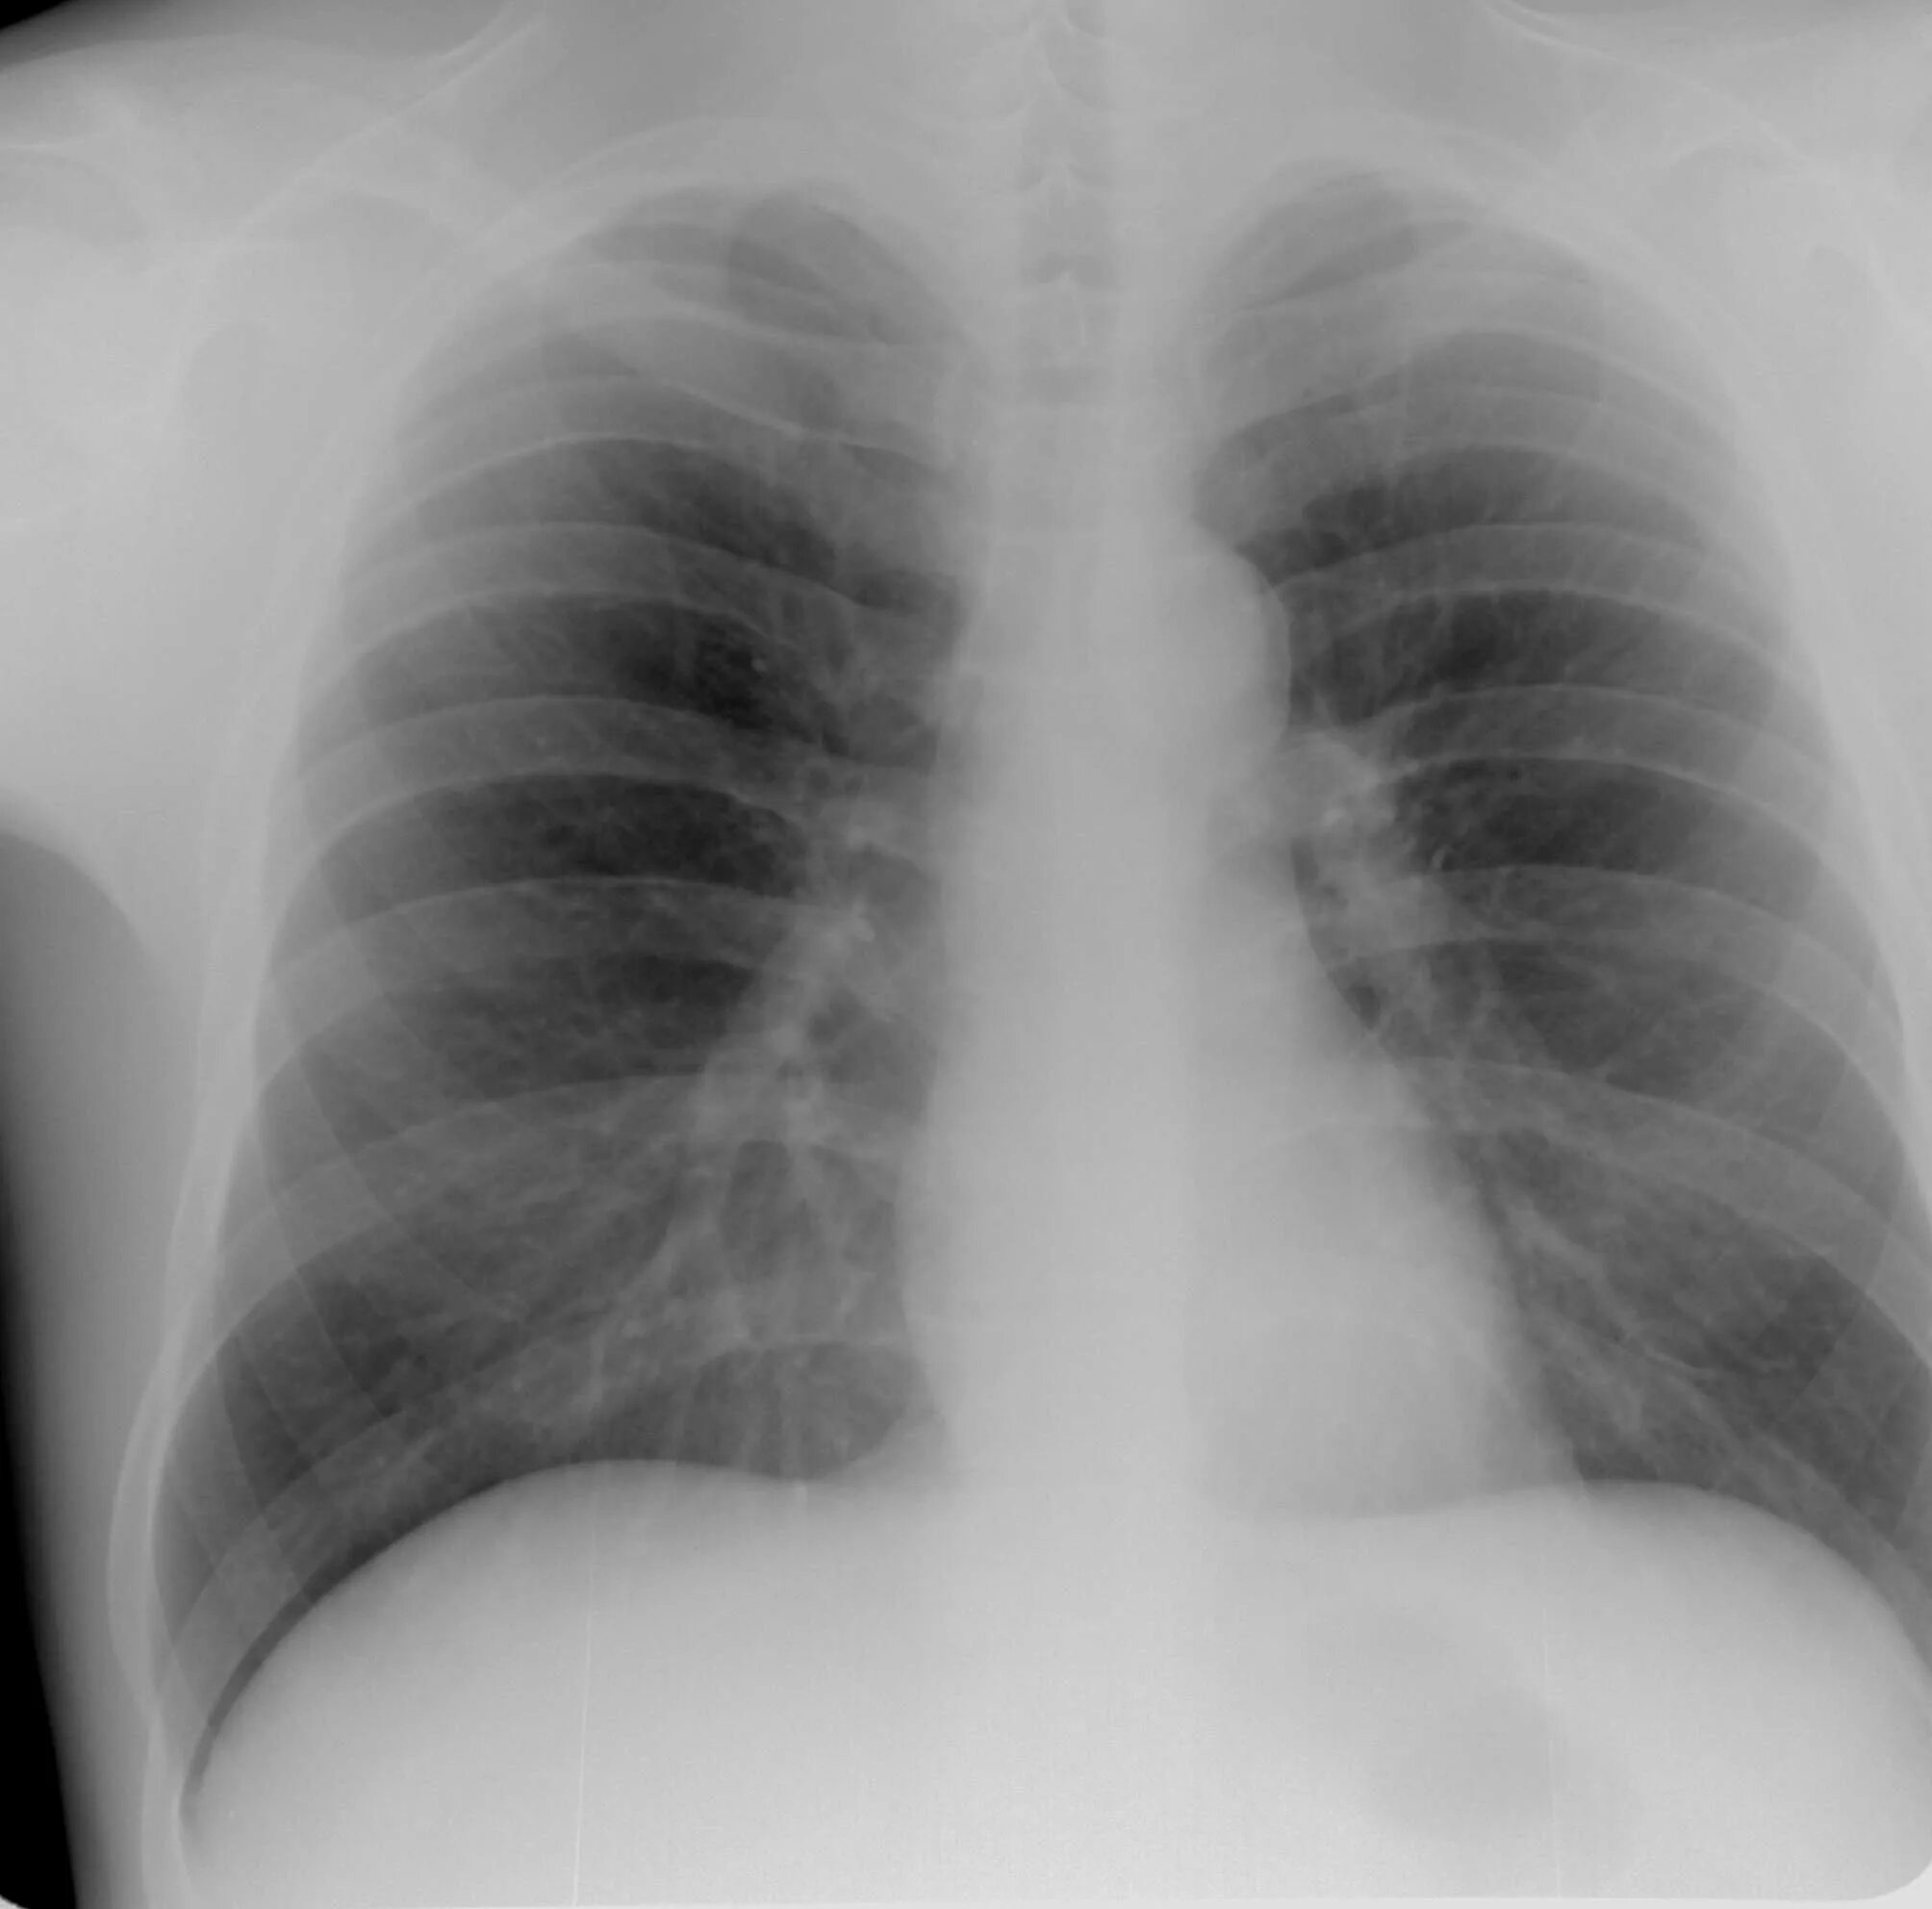

Что такое аортосклероз легких и как лечить